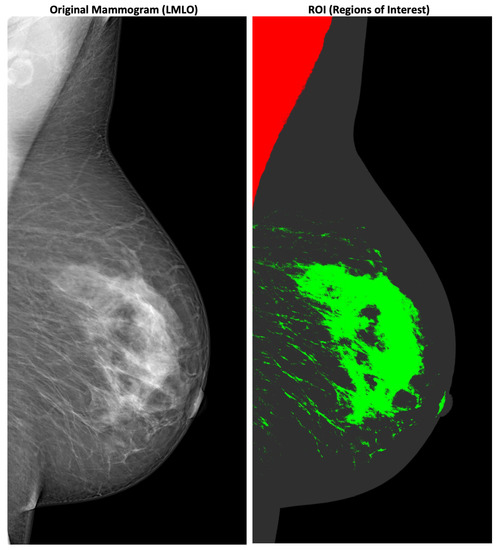

Medical image processing has been of interest since Wilhelm Röntgen discovered X-rays in 1895 [8]. The invention of Magnet Resonance Imaging (MRI) and Computer Tomography (CT) scans in the 1970s directly led to the production of digital images of a physical structure such as the human body [9,10]. Viewer applications such as the Digital Imaging and COmmunications in Medicine (DICOM) Viewer [11] provide a 3D experience for viewing medical images and extracting their relevant medical features, and hence offer innovative and accurate diagnostics. Medical image (and video) processing is important in modern healthcare. Modern technologies, e.g., Machine Learning (ML) or big data, are employed to detect, e.g., tumors or regions of interest automatically, which can produce highly annotated multimedia assets. Doctors’ letters are written in digital form and available for automated processing. Additionally, the quality and the Level of Detail (LOD) of technologies such as X-rays have increased significantly since their discovery in 1895. Analyzing X-ray images is increasingly supported by ML technologies. One example of this is the detection of tumors or regions of interest in X-ray mammograms to detect breast cancer [12]. As illustrated in Figure 1, medical images are typical examples of multimedia content including markups, overlays, descriptors, and detected features.

Figure 1. Example of a X-ray mammography with highlighted medical image features [7].